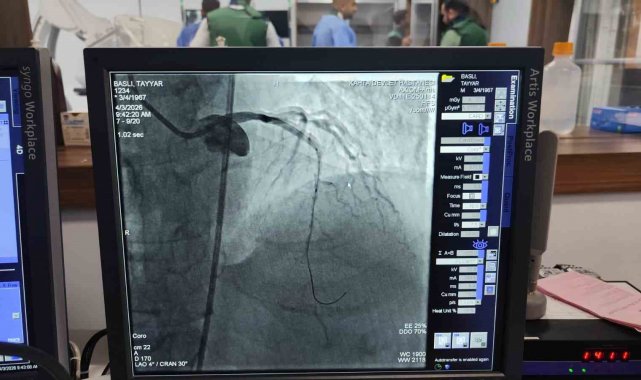

Kâhta Devlet Hastanesi Başhekimi Dr. Mustafa Akel, "Hastanemizden 45 km mesafede ikamet eden 59 yaşındaki hastamız, göğüs ağrısı şikâyeti ile hastanemize başvurmuştur. Yapılan tetkiklerde kalp krizi geçirdiği tespit edildi ve acil bir şekilde yeni açmış olduğumuz anjio merkezimize hastayı aldık. Yapılan görüntülemede kalbinin ön damarı olan LAD mid bölgesi total tıkalı tespit edildi. Hastamızın kalbinin ön damarına iki adet stent takarak tam açıklık sağlandı. Hastamızın genel durumu iyi olup yoğun bakıma takip amacıyla alındı" dedi.

Kalp ve damar hastalıklarının tanı ve tedavisinde önemli bir eksikliği gidermesi hedeflenen anjiyo ünitesi, hizmete alınmasının hemen ardından ilk vakasını kabul etti. Kalp krizi şüphesiyle Kâhta Devlet Hastanesi Acil Servisi'ne başvuran hasta, yapılan ilk müdahalenin ardından vakit kaybetmeden anjiyo ünitesine alındı. Burada gerçekleştirilen operasyonla hastanın kapalı olan iki damarına stent takıldı. Müdahalenin ardından hastanın genel sağlık durumunun iyi olduğu öğrenildi.